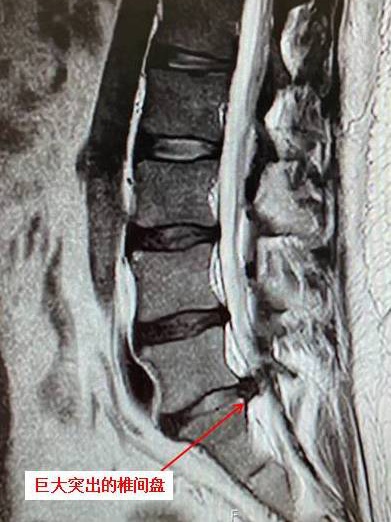

小张慕名来到同济大学附属同济医院骨科就诊,谢宁主任医师给他做了磁共振检查,发现有巨大腰椎间盘突出,腰椎管狭窄,压迫神经很严重;而且经过彻底检查,发现他左脚的力量已经有所下降,遂决定尽快进行手术治疗。

磁共振显示腰5骶1巨大突出的椎间盘